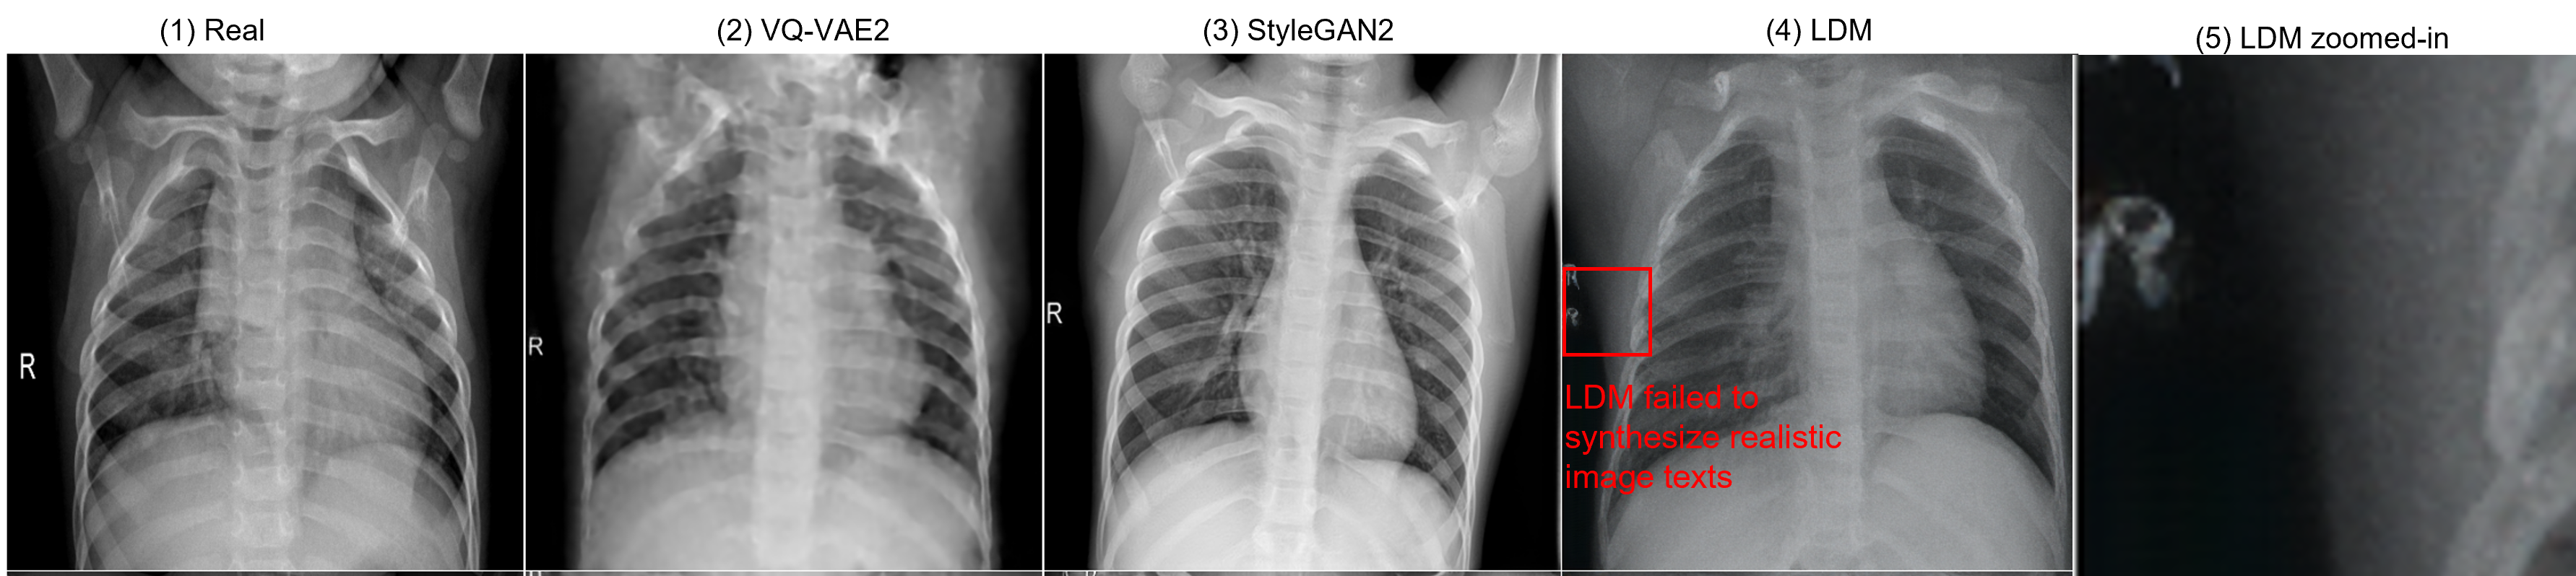

Figure 4: Examples of X-ray datasets (Normal). The LDM model failed to synthesize realistic image texts, thus producing synthetic images that did not look real.

Fig. 3 shows that the LDM mode did not inherit the dataset bias. Thus, we visualized several example images from real and synthetic datasets. In Fig. 3, the LDM model tried to capture the dataset bias, while it failed to synthesize realistic image texts and thus failed to capture the real but biased dataset distribution. This failure, however, turned out to increase the robustness of the feature extractor trained on the LDM-synthesized images.